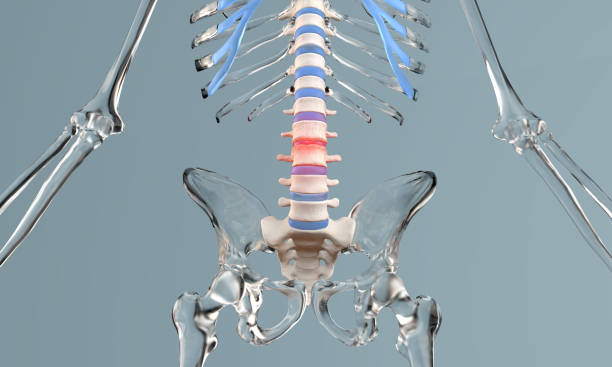

요추 전만은 허리디스크 치료와 예방에서 핵심적인 역할을 합니다. 요추 전만을 만들면 디스크의 압력이 감소하고 허리디스크 증상을 완화할 수 있습니다. 이를 위한 두 가지 자세가 있습니다.

1. 오리 궁둥이 방법

오리 궁둥이 방법은 골반을 앞으로 돌리면서 엉덩이를 뒤로 빼는 자세입니다. 이 자세를 취하면 요추 전만 곡선을 만들게 됩니다.

하지만 주의할 점은 오리 궁둥이 방법은 디스크 손상을 쉽게 일으킬 수 있으므로, 이 자세를 유지하려면 등 뒤에 있는 근육을 강하게 수축시켜야 합니다. 이로 인해 디스크 내부의 압력이 높아져 디스크가 더 찢어질 수 있습니다.

2. 당당한 가슴 방법

당당한 가슴 방법은 골반을 그대로 고정하고 척추의 뒷부분만을 뒤로 젖혀 요추 전만 각도를 만드는 자세입니다. 이 자세는 상체 무게가 허리 뒤로 떨어지게 되어 디스크에 압력을 덜 가하게 합니다.

디스크 압력이 낮아지므로 허리디스크 증상을 완화하는데 도움이 됩니다.